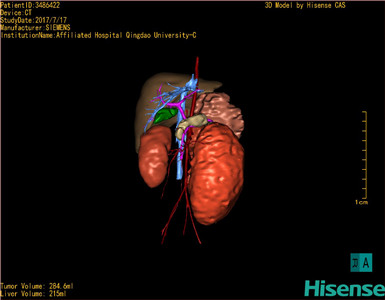

肾母细胞瘤-CH-001-N-001503

CT结果输入海信CAS系统后行3D重建及手术规划后,于2017-7-21全麻下行“左肾切除术”手术治疗:

术前三维重建及手术方案设计:

将0.625mm双源薄层CT资料的静脉期和动脉期Dicom格式文件导入海信CAS系统。

通过调节窗宽窗位调整CT序号,对肿瘤,肝实质,胆囊,下腔静脉,肿瘤,肝动脉、门静脉及肝静脉等进行三维重建;系统自动计算肿瘤体积和肝脏体积。

模拟手术操作,自动计算切除肿瘤体积。肝脏体积为215ml,肾脏肿瘤大小为284.6ml通过术前模拟手术,精准判断手术可行性。

术前三维重建:

重建图片